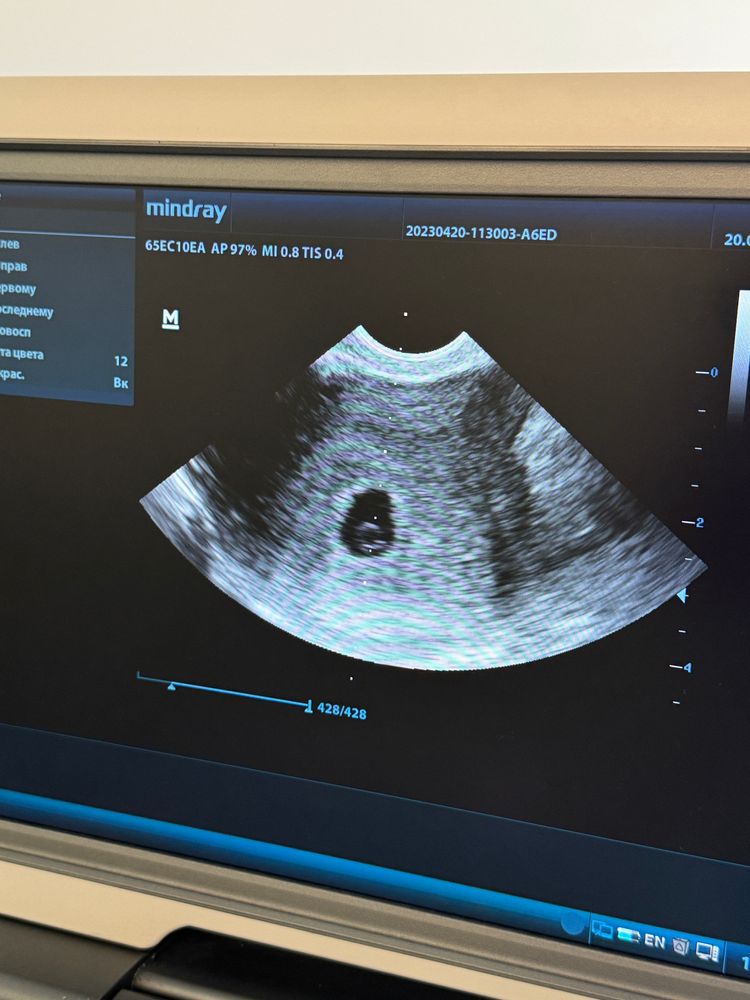

6 акушерских недель, не видно эмбриона

сегодня сдала 19.06 ХГЧ - 6300 мМЕ/ мл

Еще и не могут увидеть эмбрион , хотя наверное уже должны были , поставили повтор 27 июня (будет 7 неделя) очень переживаю , так как ранее была ЗМ